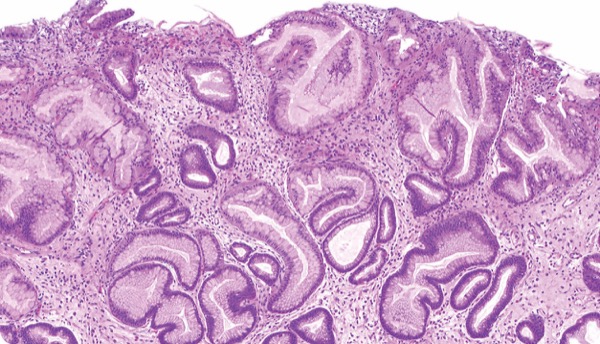

Three patients developed gastric cancer over the median 30.5-month follow-up period (IQR, 11.1-61.2; 0.3%; cumulative incidence, 1.37% [95% CI, 0.43%-4.30%]). During the study period, 515 GHPs were resected, and neoplasia was found in six polyps (1.2%). All those polyps were 20 mm or greater in size, and five of the six had pedunculated morphology.

The researchers concluded that pedunculated polyps that are 20 mm or larger may require resection because they are the most likely to harbor neoplasia, but they urged a more restrictive approach when removing smaller polyps.